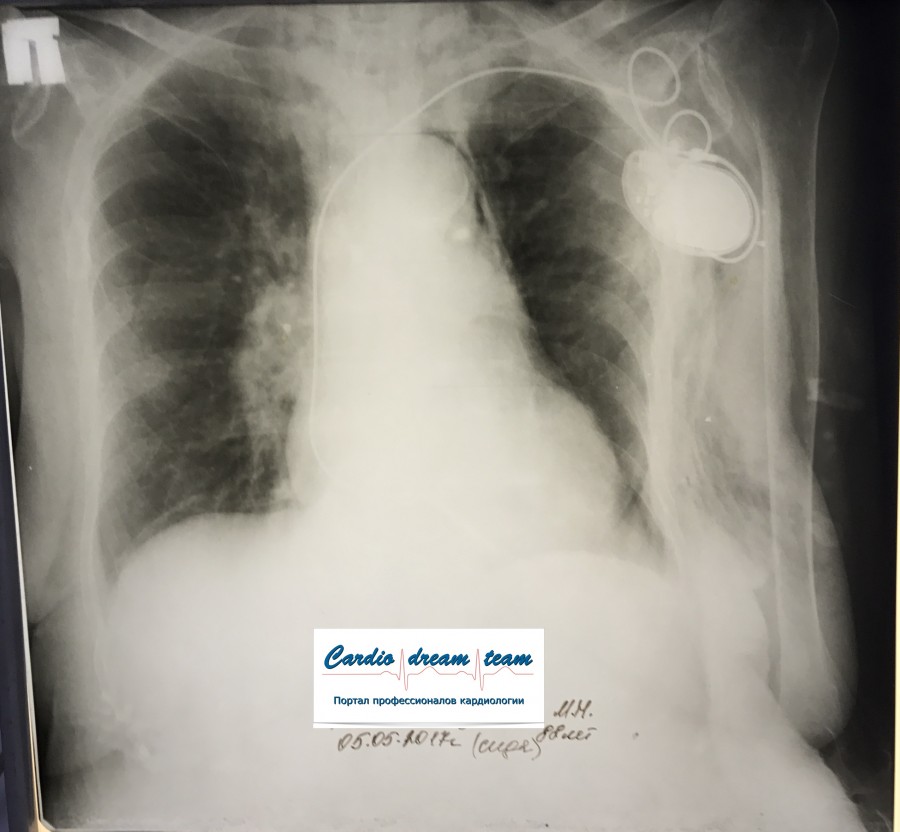

ИССЛЕДОВАНИЕ ОРГАНОВ ГРУДНОЙ КЛЕТКИ Дата 01-ОКТ-15 время 11.30 ОПИСАНИЕ: Проведена рентгенография органов грудной клетки в прямой проекции, положение сидя, условия ПИТ, Р-контроль Легочные поля: Справа легкое расправлено не полностью, апикально до 3го ребра прослеживается свободный газ в плевральной полости. Тень дренажа справа. Тень подключичного катетера в проекции ВПВ. Легочный рисунок: сгущен справа в прикорневой зоне, диффузно деформирован Корни: малоструктурны, обогащены Синусы: нечеткие Сердце: широко лежит на диафрагме (позиционно) ЗАКЛЮЧЕНИЕ: Течение правостороннего пневмоторакса, положительная Р-динамика. Состояние дренирования правой плевральной полости. Р-признаки полнокровия сосудов МКК. Пневмосклероз. Р-контроль .────────────────────────────────────────────────────────────────────── ИССЛЕДОВАНИЕ ОРГАНОВ ГРУДНОЙ КЛЕТКИ Дата 02-ОКТ-15 время 1015 ОПИСАНИЕ: